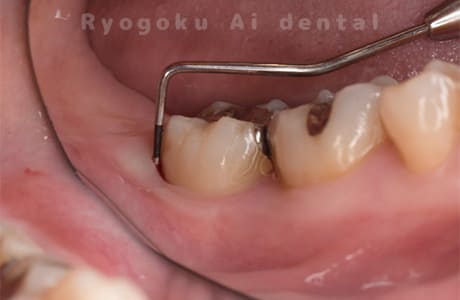

長年、右下からの出血が止まらないということで来院された患者さんです。衛生士さんとのブラッシング指導、並びに、歯石のお掃除を終えても歯周ポケットの改善がなかったため、再生療法を行いました。歯周ポケットが約7ミリ存在した部分が4ミリに改善し、出血もなくなりました。